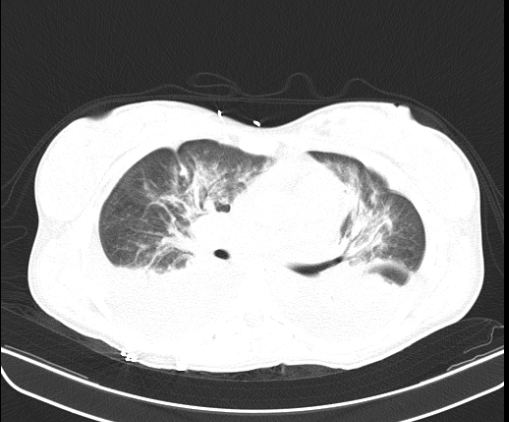

Pyelonephritis was again documented, for which the patient was hospitalized to start intravenous in-hospital antibiotic management (ampicillin/sulbactam, 3 g IV every 6 hours) and a urine culture was requested, renal and urinary tract ultrasound was performed, reporting a finding of bilateral hydronephrosis. grade II without findings of renal lithiasis or other alterations (figure 1). Patient who remained 4 days of hospitalization under antibiotic treatment mentioned above with stable evolution, however, on the 5th day of hospitalization he presented abrupt torpid evolution of his clinical picture with blood pressure figures with a tendency to hypotension, tachypnea, tachycardia (blood pressure 80/50mmHg, respiratory rate 28rpm, heart rate 112lpm, wakes up to verbal stimulation) (omSOFA: 2pts), then considering a diagnosis of sepsis of urinary origin, for which it was indicated to stagger antibiotic treatment to piperacillin/tazobactam at a dose of 4.5gr IV every 8 hours, a bolus of 2000cc (30cc/kg) was administered and basal fluids were continued at 100cc/hr; extension laboratories for sepsis were requested (Table 3) and transfer to the intensive care unit for comprehensive management was indicated. PT: prothrombin time, INR: international normalized ratio, PTT: partial thromboplastin time, CR: creatinine, LDH: lactic dehydrogenase, BUN: urea nitrogen, WBC: White blood cells, N: neutrophils, HB: hemoglobin, HTO: hematocrit, PLT: platelets. CRP: C-reactive protein, CL: chlorine, K: potassium, NA: sodium Based on platelet count findings, dengue with warning signs was considered as a differential diagnosis because it was located in an endemic area; but this diagnosis was later ruled out by both negative dengue IgG and IgM antibody tests. During her stay in the High Obstetric Risk Intensive Care Unit (seventh day of hospitalization and second day in the unit), she was assessed by the intensive medicine and critical care service, who, taking into account the intermittent fever, hypotension and systemic inflammatory response (tachycardia, tachypnea) despite management with broad-spectrum antibiotics (4 days of ampicillin/ sulbactam and two days of piperacillin/tazobactam at the doses described) and optimal fluid therapy, they consider a patient with septic shock and decide to start adjuvant therapy in the context of urinary focus shock with immunoglobulin G enriched with IgM and IgA at a dose of (5ml/kg/day) for 3 days. The patient's clinical evolution was monitored and she had persistent tachycardia (102 bpm) without tachypnea and without new febrile episodes. She was assessed by the infectious disease service (eighth day of hospitalization and third day in the unit) who considered continuing antibiotic escalation to ertapenem 1gr IV every 24 hours for 7 days due to persistent tachycardia and continuing with the last dose of immunoglobulin G enriched with IgM and IgA. The patient continued with satisfactory evolution, with blood pressure figures at goals, without requiring vasopressor support, with a progressive increase in platelet levels and improvement in the blood cell count (Table 4). On day 4 of intravenous antibiotic therapy with ertapenem (twelfth day of hospitalization, seventh day in the unit) the patient suddenly became tachypneic with saturations of 88%, for which a chest tomography was indicated (figure 2 and figure 3) where It showed a large left pleural effusion, which is why a thoracentesis was indicated, draining 620 cc of clear liquid without infectious characteristics in the bacterial culture cytology reading and a negative fungal test. Patient with immediate improvement after drainage of the pleural effusion; for which she was transferred to a general gynecological hospitalization receiving antibiotic treatment with stable vital signs, afebrile, without loss of fetal well-being evaluated by obstetric ultrasound, who completed antibiotic treatment and proposed adjuvant immunotherapy scheme with immunoglobulin G enriched with IgM and IgA with adequate drug tolerance and favorable clinical course.